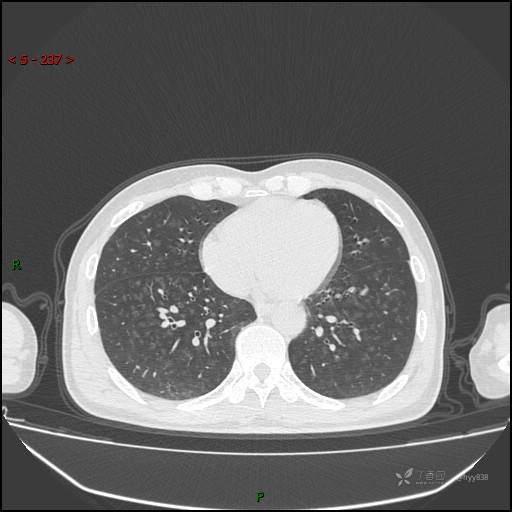

性别:男

年龄:55岁

简要病史:渐进性呼吸困难。

实验室检查:血象正常。

临床诊断:呼吸困难待查

胸部CT平扫

电焊工尘肺 (2)